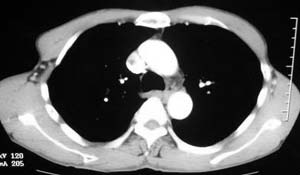

患者,男,58岁,煤矿职工,无症状,单位体检发现病变。

肺窗显示结节的后外边缘呈分叶状生长系生长过程受血管阻挡所致,出现较典型的“树凹”征,部分边缘见毛糙,不均匀强化,楼主未提供增强前后ct值,不好比较,倾向周围型ca。

右肺门上缘见类圆形节结影,密度尚均,边缘清楚,其内可见点状钙化影,周围支气管受压移位,病灶未见明显强化。考虑:1炎性假瘤  2 支持周围型肺ca (腺瘤)

右肺门上缘见类圆形节结影,密度尚均,边缘清楚,其内可见点状钙化影,周围支气管受压移位,病灶未见明显强化。考虑:良性病变——结核球可能性大,周围型肺癌待排。

病灶边缘光滑,似可见分叶征,未见明显毛刺。气管影轻度向右偏移。内可见点样钙化。邻近气道影通畅,考虑结核球可能。请楼主尽快公布结果

右肺门上缘见类圆形结节影,密度尚均,边缘清楚,其内可见点状钙化影,周围支气管受压移位,病灶未见明显强化。考虑:良性病变;首先考虑肺内错构瘤。次考虑肺内腺瘤。

病灶呈分叶型,边缘清晰,无毛刺,增强强化不明显,内见多发钙化,亦无卫星灶。多考虑良性病变。错构瘤可能性大。

病灶呈分叶型,边缘清晰,无毛刺,增强强化不明显,内见多发钙化,亦无卫星灶。多考虑良性病变。错构瘤可能性大或结核球。肺癌待排

动脉相上,右上肺动脉的尖段分支位于结节旁,结节对血管形成压迫而使到走行略改变,并没有很明确的包绕,也没有动脉期的供血,考虑还是偏向于良性可能大。当然最后的决定还是病检

病变边界清晰,对周围主要是外压性改变,未见血管包绕,边缘及中心见钙化,考虑良性病变,结核球可能